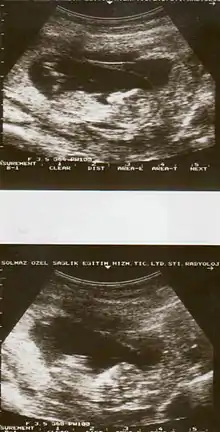

يتم تشخيص انفصال المشيمة المبكر عند اكتشاف ألم أو نزيف مهبلي بالفحص الإكلينيكي، و زيادة حجم الرحم (ارتفاع مستوى قاع الرحم) مقارنة بالحجم الطبيعي للجنين حسب سنه.

ثم الفحص بالموجات فوق الصوتية المجدي في بعض الحالات[7] ، و قد تستخدم أشعة الرنين المغناطيسي إذا لم تنجح الموجات فوق الصوتية، يليها اختبارات التجلط لدم الأم و مراقبة لحالة الجنين.[3]